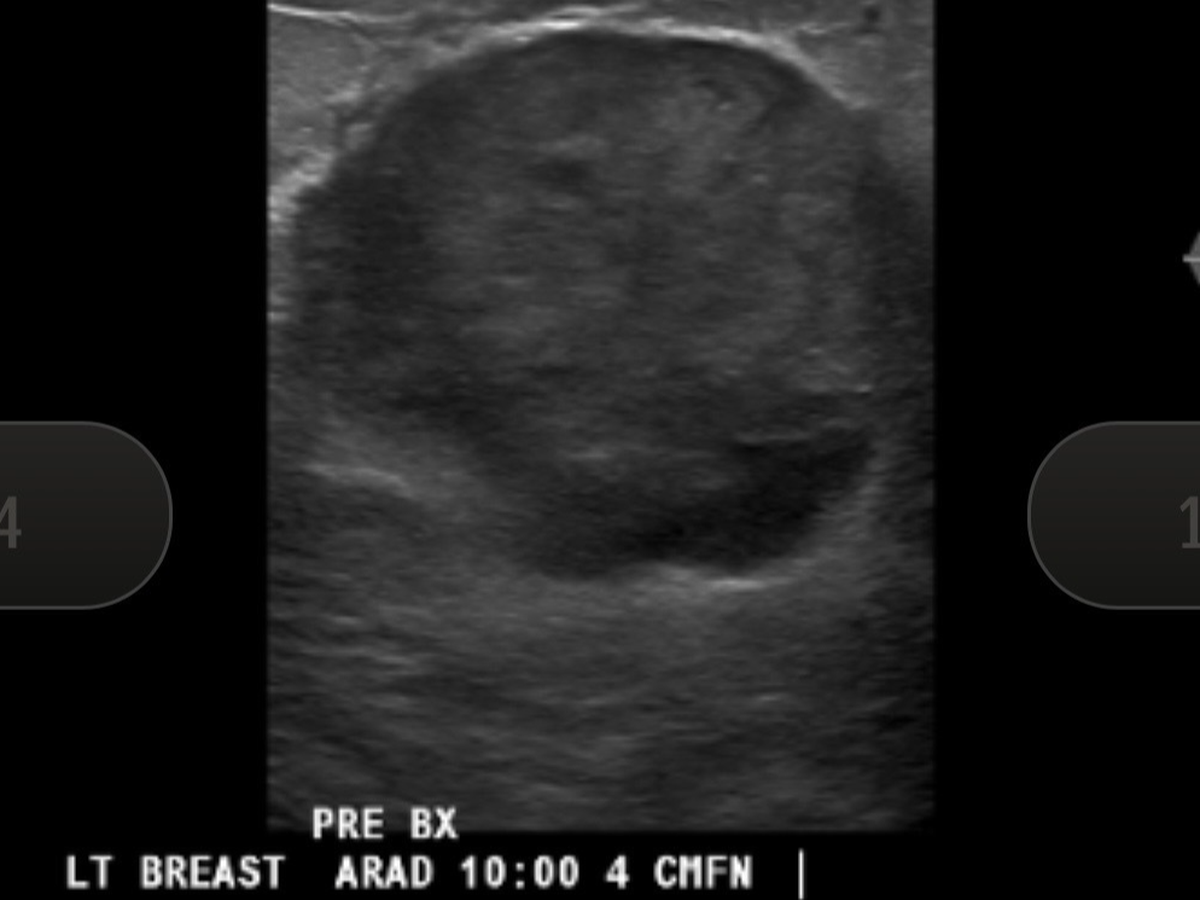

In November, I went in for a routine OBGYN appointment. Nothing exciting. No drama. I had what I thought was a cyst in my left breast. Had one before - no big deal.

Cut to January: diagnostic mammogram, ultrasound, biopsy the following week.

On January 27, I was diagnosed with metaplastic triple negative breast cancer — a rare and aggressive form of breast cancer that’s sneaky and likes to spread to distant organs via the bloodstream.